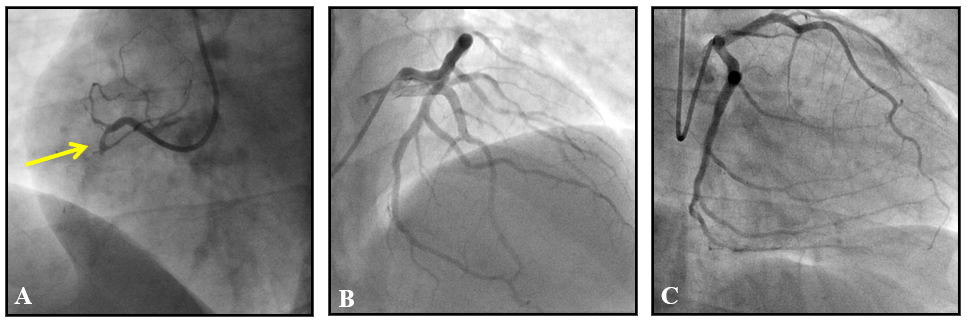

Figure 2 (A) Right coronariography in left oblique projection demonstrating occlusion of right marginal branch in proximal segment (arrow); (B) left coronary angiography in caudal projection; C: left coronary angiography in cranial projection; both showing no significant obstructive lesions in the other coronary arteries.

Figure 5 (A) right coronary angiography in left oblique projection demonstrating total occlusion of the non-dominant right coronary in its proximal portion (arrow); (B) left coronary angiography in direct cranial projection demonstrating mild obstructive lesion in diagonal branch; (C) left coronary angiography in right obliquous projection demonstrating dominant circumflex branch with mild obstructive lesion in its proximal portion.